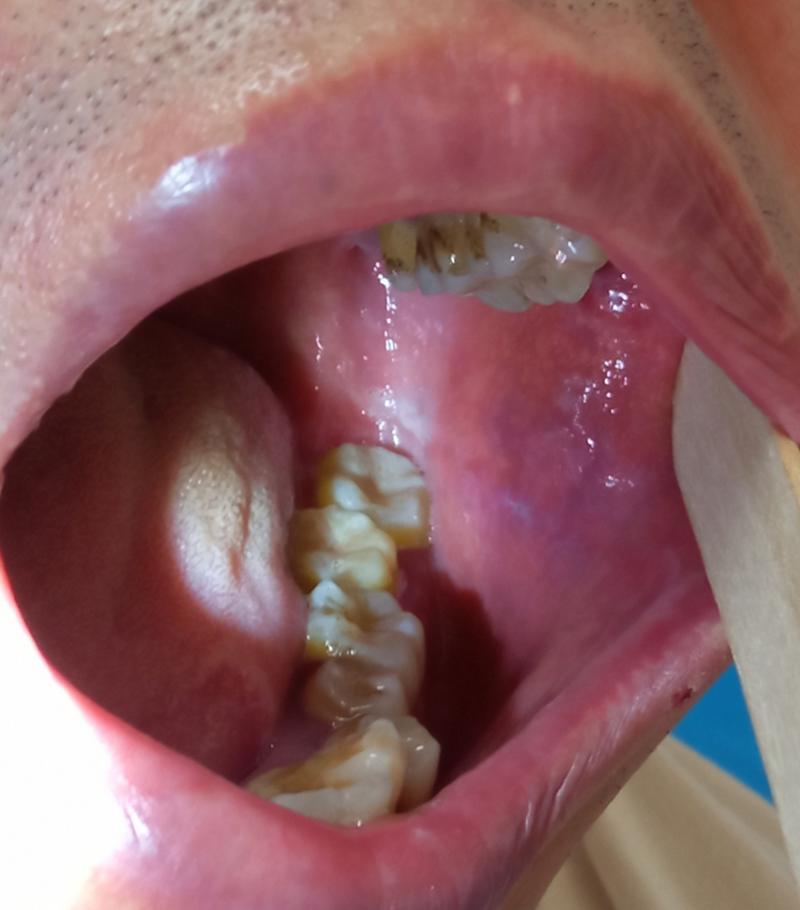

口腔最里边的牙龈肿痛 下面我为您详细分析可能的原因、可以尝试的家庭缓解方法,以及何时必须去看医生。 最可能的原因:智齿冠周炎 这是导致最里边牙龈肿痛的首要原因。 什么是智齿冠周炎? 智齿(第三磨牙)在萌出过程中,由于空间不足,无法完全正常地长出来,会部分被牙龈组织覆盖,这个牙龈瓣和牙齿之间形成了一个盲袋,叫做“龈瓣袋”,...